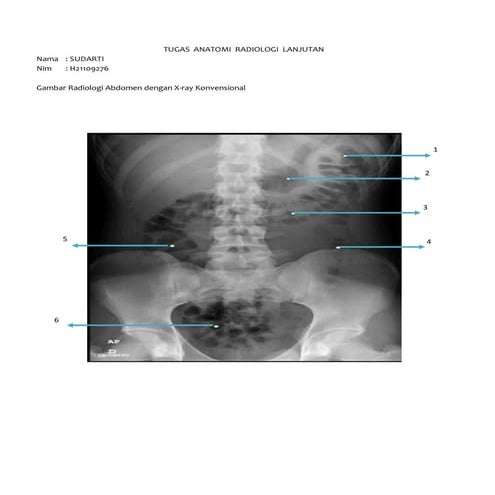

X ray (kel x)